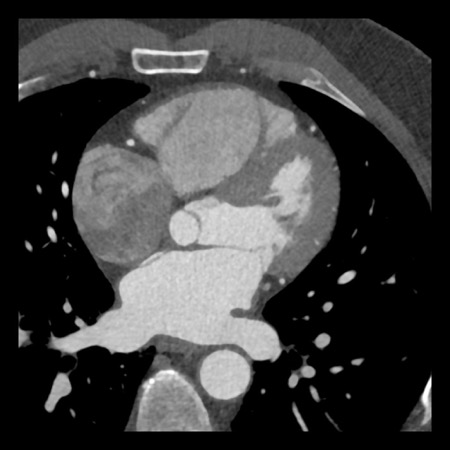

case 1 – CAD-RADS 2/P1

First, scroll through the scan.

Not all images are included. Some images without any abnormalities are skipped

from the series.

How would you describe the findings on the coronary CTA?

The findings are:

- Agatston score of

this patient was 14 (P1). Please, also note the calcification of the aortic valve. - Some partially

calcified and calcified plaques are present in the LAD with mild stenosis

(25-49%). - Calcified-plaque in

the LCX causing minimal stenosis (<25%). - Non-calcified

plaque in the distal RCA causing minimal stenosis (<25%). - This patient classifies

as CAD-RADS 2/P1, which means no further workup is needed.